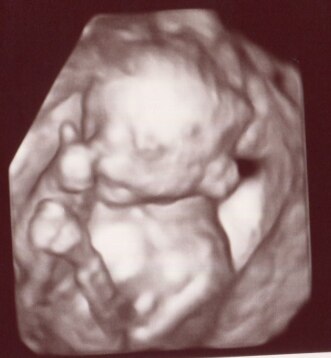

schon in der Nase bohren :) Unsere kleine Maus ist beim heutigen US ein Mädchen geblieben (ist nichts gewachsen *lach*) aber sie hat ganz viele faxen gemacht heute :) sie hatte ja eine menge Nachzuholen denn bei den letzten US hat sie sich ja nur wiederwillig ein bischen bewegt :)

Bild zu Ultraschallbild... noch garnicht auf der Welt aber... - Schwanger - wer noch? Rund um die Schwangerschaft